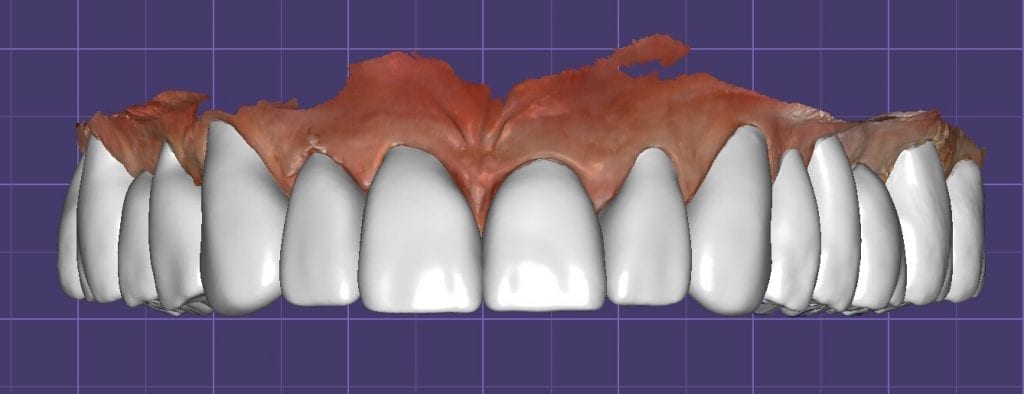

The digital models were then imported into a third party software where a library of tooth morphologies are available for the clinician to choose from.

Once the appropriate library is chosen, the digital wax ups are performed. In the subsequent photos you can see the transparent overlay of the wax-ups to the original position of the existing dentition